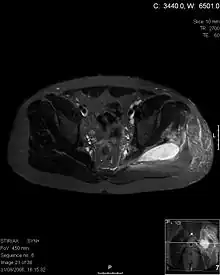

| Transverse T2 magnetic resonance imaging section through the hip region showing abscess collection in a patient with pyomyositis. | |

| Diagnostic method | Diagnostic method used for PM includes ultrasound, CT scan and MRI. Ultrasound can be helpful in showing muscular heterogeneity or a purulent collection but it is not useful during the first stage of the disease. CT scan can confirm the diagnosis before abscesses occur with enlargement of the involved muscles and hypodensity when abscess is present, terogenous attenuation and fluid collection with rim enhancement can be found. MRI is useful to assess PM and determine its localization and extension |

Axial T1 weighted fat suppressed post IV gadolinium contrast enhanced MRI image showing a mutliloculated bacterial abscess in the left gluteal muscle which grew Staphylococcus aureus (methicillin sensitive) thought to be due to tropical pyomyositis.

Coronal fat suppressed post contrast image showing a multiloculated bacterial abscess in the left gluteus minimus muscle due to tropical pyomyositis.

Coronal T2 weighted fat suppressed image showing a multiloculated fluid collection in the left gluteal musculature due to tropical pyomositis in a 12-year-old boy.